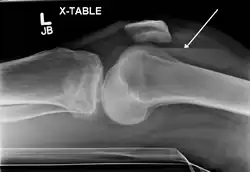

In all injuries to the tibial plateau radiographs (commonly called x-rays) are imperative. Computed tomography scans are not always necessary but are sometimes critical for evaluating degree of fracture and determining a treatment plan that would not be possible with plain radiographs.[10] Magnetic Resonance images are the diagnostic modality of choice when meniscal, ligamentous and soft tissue injuries are suspected.[11][12] CT angiography should be considered if there is alteration of the distal pulses or concern about arterial injury.

Lipohemarthrosis (presence of fat and blood from bone marrow in the joint space after an intraarticular fracture) seen on X-ray in a person with a subtle tibial plateau fracture -

Lipohemarthrosis due to a tibial plateau fracture -

A tibial plateau fracture seen on X-ray